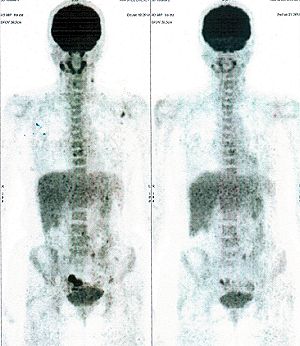

Below are some of the cases, from more than 80 cases we have treated so far with good results. When reading the PET/CT scans, the picture on the left is before treatment, and the picture on the right is after treatment. The intensity of black represents the activity of the cancer, but some black areas are not cancer: brain, heart, radioactive urine in bladder. For the heart, the intensity of black depends on the number of hours of fasting: if more than 10 hours, the heart is not even black, but if fasting is less than 6 hours, it is very black. The intensity of black in the brain can be variable in different scans depending on the brain activity at the time of the scan. The intensity of black in the radioactive urine can also be variable due to the hydration of patients and the time of injection of diuretic.

CASE NO: 1

(HEPATOCELLULAR CARCINOMA + STOMACH CANCER)

A middle-aged women who is very thin and very weak, can hardly walk, lying in bed most of the time. She saw a cancer specialist in a top hospital who discovered that she had massive hepatocellular carcinoma, and another cancer in the stomach. Given that hepatocellular carcinoma is incurable and stomach cancer is very difficult if not impossible to cure without surgery, she was told that nothing could be done for her. She came to ask us to help her. After just 4 treatment, the hepatocellular carcinoma went into remission, and the stomach cancer (arrow) became less active. Until today, more than 6 months later, the hepatocellular carcinoma is still in remission.